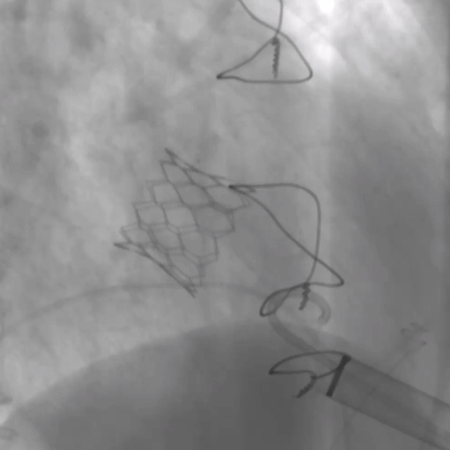

术前经详尽评估患者病情,通过CT重建测量瓣环直径、左室流出道面积。结合之前外科换瓣手术入路,决定采用经心尖途径行二尖瓣“瓣中瓣”手术。术中选用27# Renato®球扩式瓣中瓣,顺利通过心尖途径植入。手术过程顺利,几乎无出血。最终瓣中瓣植入位置理想,功能表现出色,左室造影及经食道超声观察无明显瓣中及瓣周反流。二尖瓣峰值流速由术前2.5m/s降至1.6m/s,平均跨瓣压差由11mmHg降至5mmHg。

毁损生物瓣瓣架结构 瓣环内径测量

瓣中瓣植入后无反流及瓣周漏